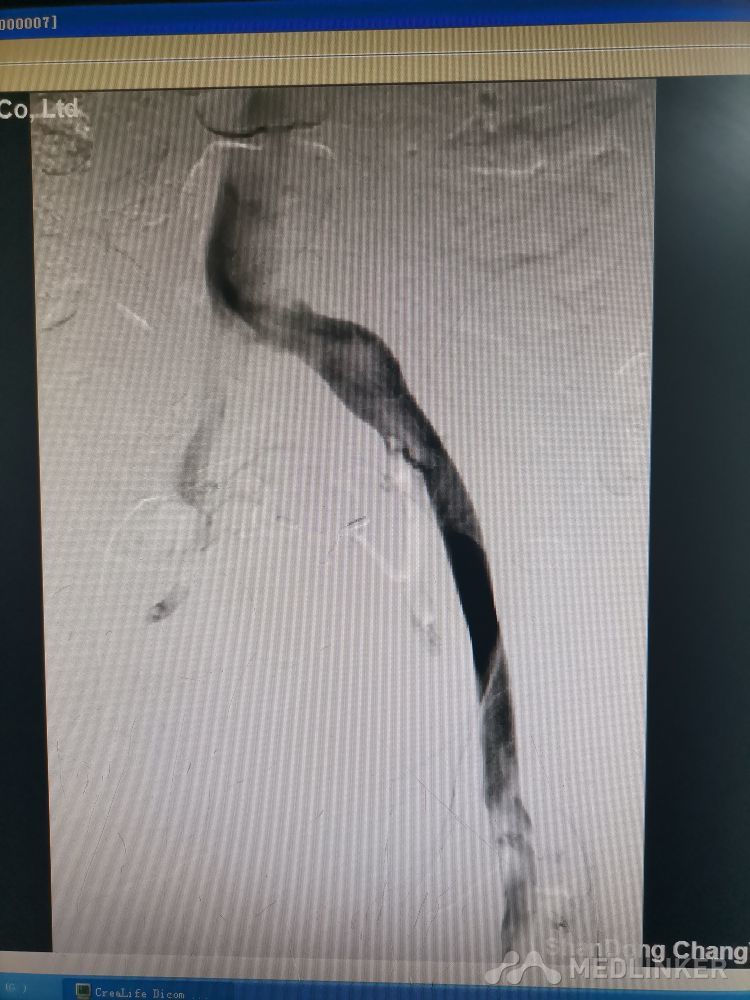

重视髂静脉压迫综合征。不同的临床表现,相同的病因,均为髂静脉压迫所致。第一例,表现为下肢静脉曲张伴溃疡,造影证实,髂静脉支架置入后解决。第二例,表现为左侧髂股静脉血栓,置管溶栓并髂静脉支架置入开通血管。第三例,下肢深静脉血栓后遗症,外院已行髂静脉支架置入,但皮肤营养情况仍持续加重,开通股浅 ,可见病变局部异常坚硬。精准施治,对症下药。